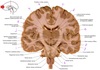

1

Q

a

body of corpus callosum

2

b

Anterior horn of lateral ventricle

3

c

Septum pellucidum

4

d

Rostrum of corpus callosum

5

e

Head of caudate nucleus

6

f

Anterior limb of internal capsule

7

g

8

h

Nucleus accumbens